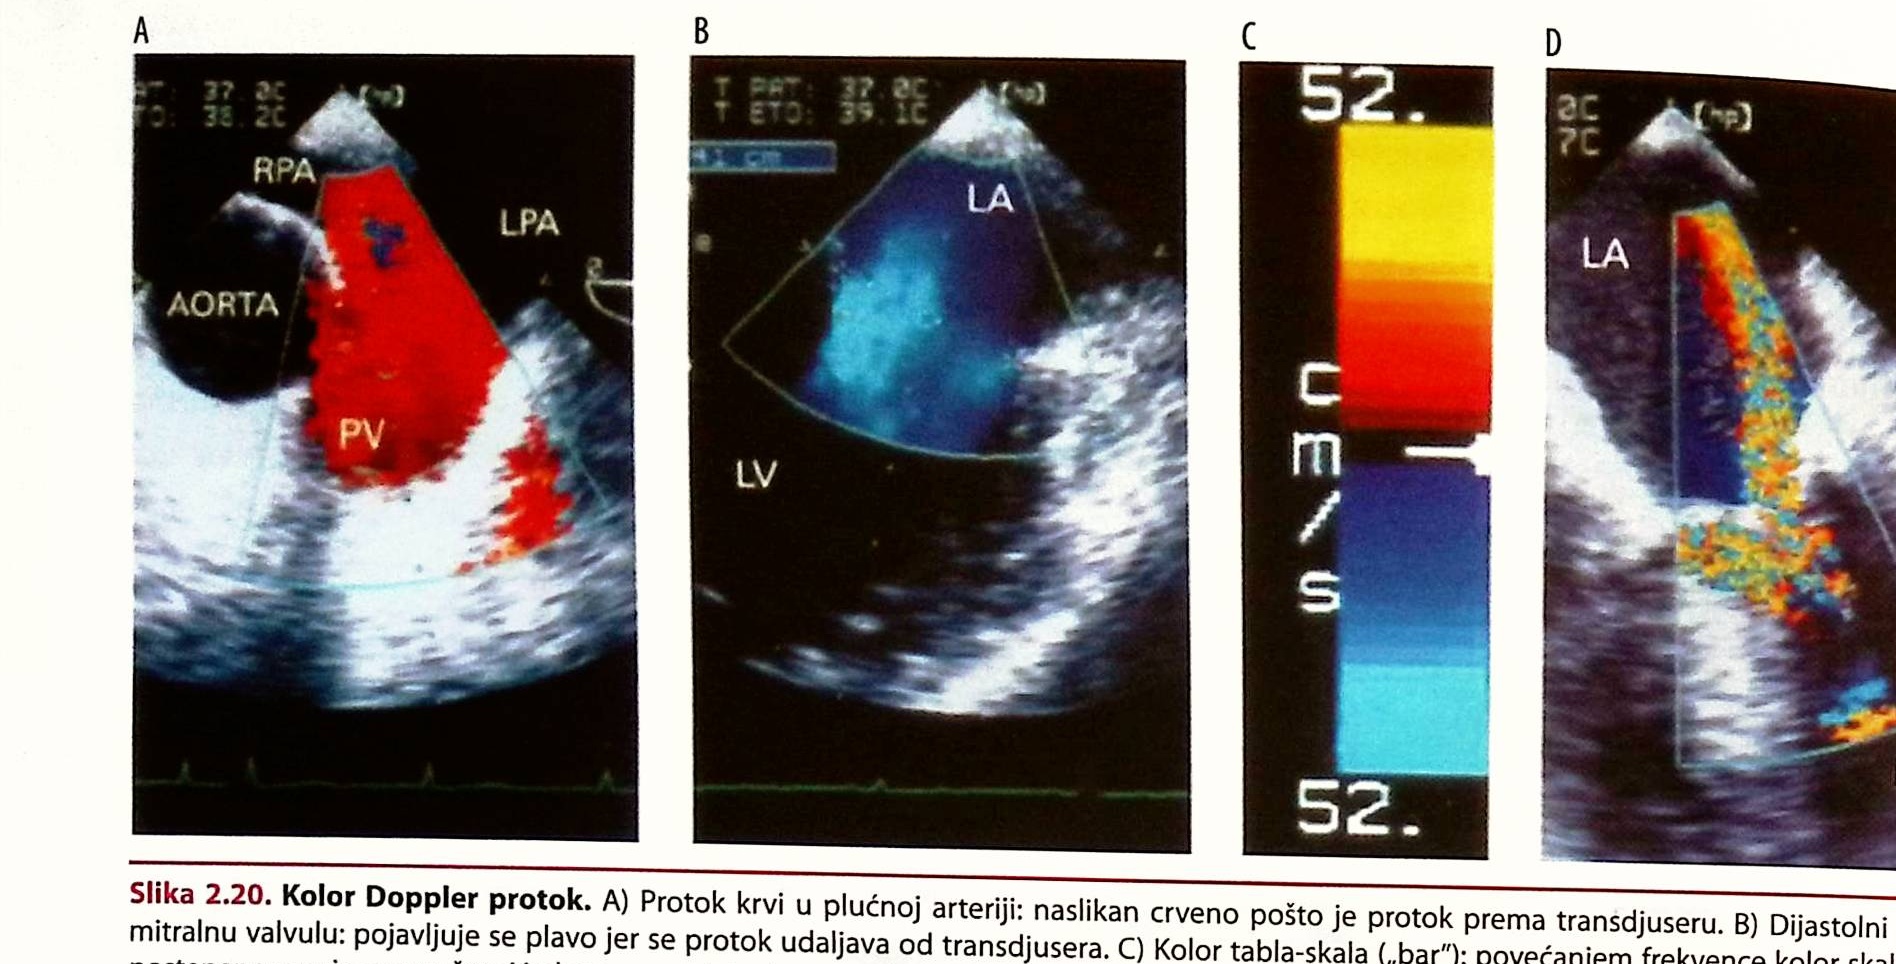

2. DOPPLER EHOKARDIOGRAFSKE TEHNIKEITEHNOLOGIJA 15